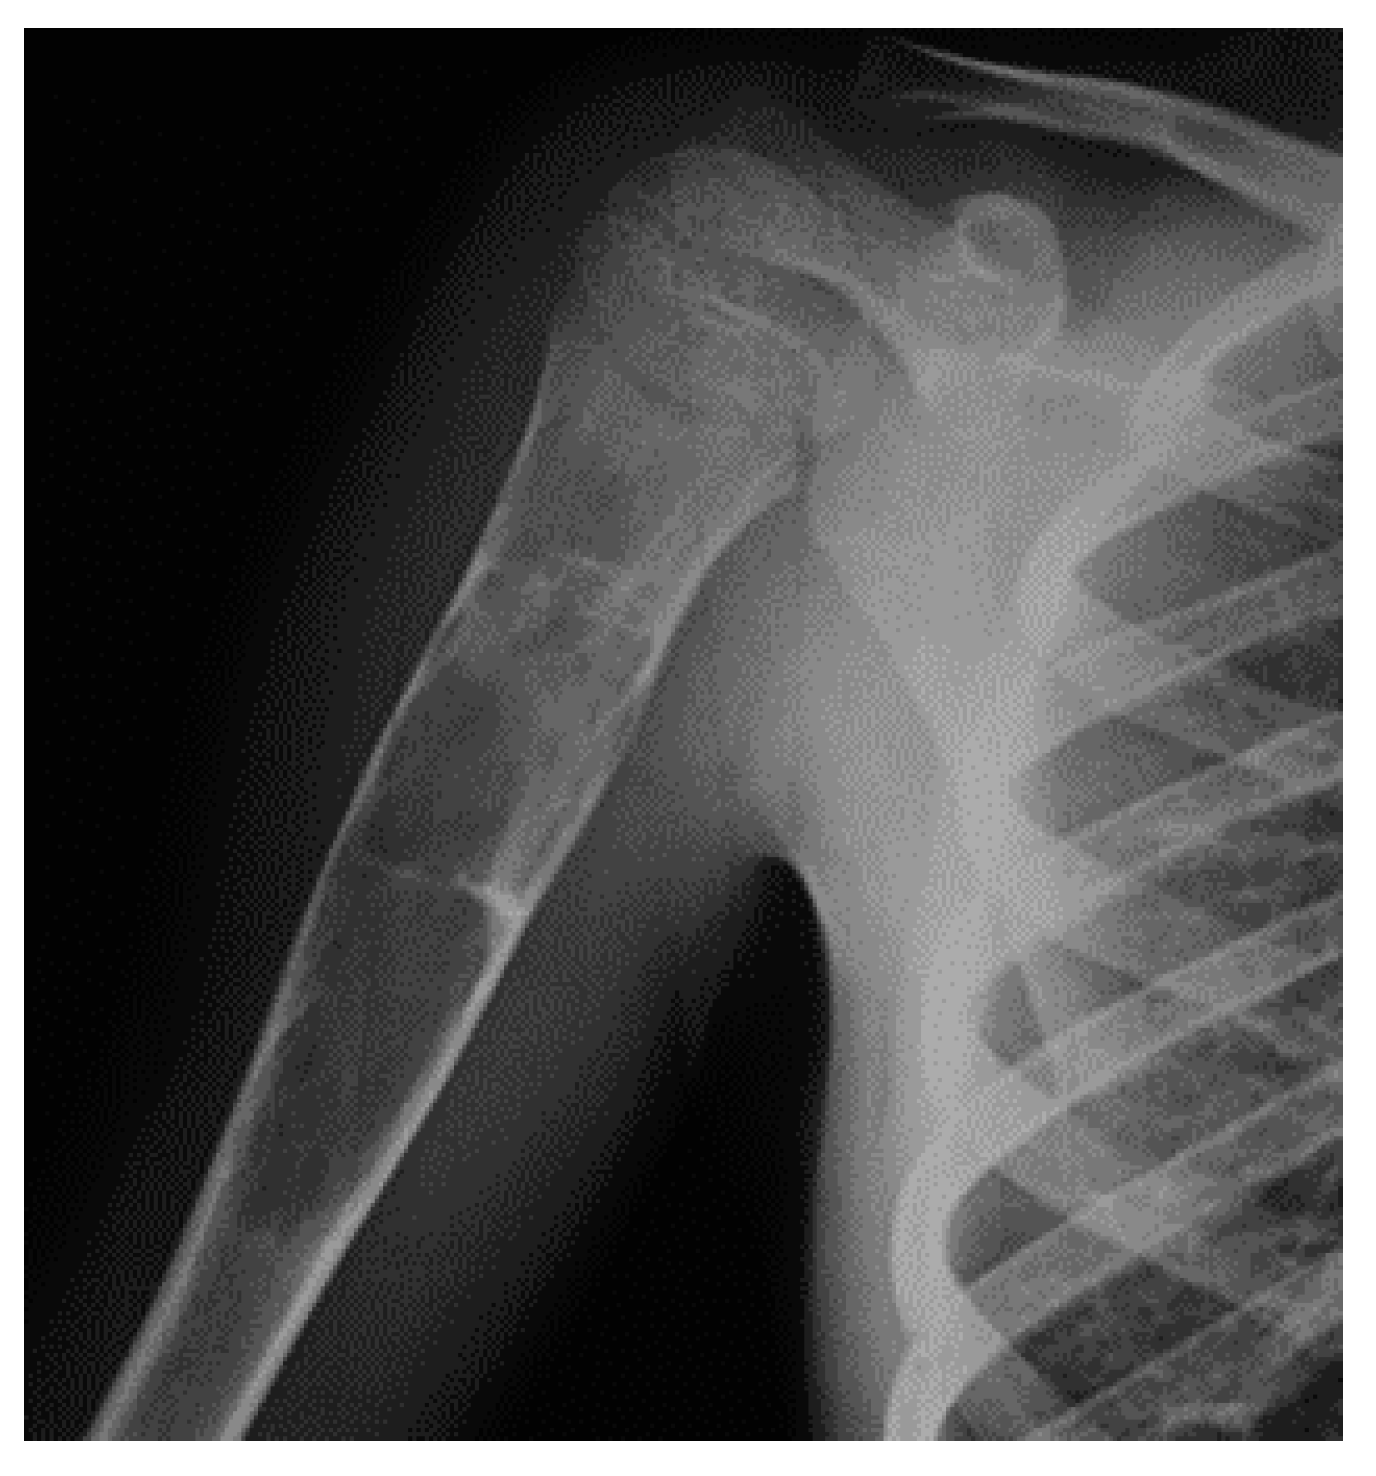

Figure 4. X-rays and CT scan of an NOF, incidentally discovered in a female patient in her 20s.

On radiographs, NOFs appear as solitary, eccentric and lytic lesions in the metaphysis of long bones, often polycyclic in shape. Typically, the lesion is lucent, and margins can appear densely sclerotic or indistinct, as well as the cortex, which may be thinned or, in some cases, thickened. When multiple, the most significant length of the lesion is oriented on the long axis of the bone [101]. NOF can spread, causing a thinning of the diaphyseal cortical bone with interspersed sclerosis and anterior or anterolateral bowing (Figure 4).